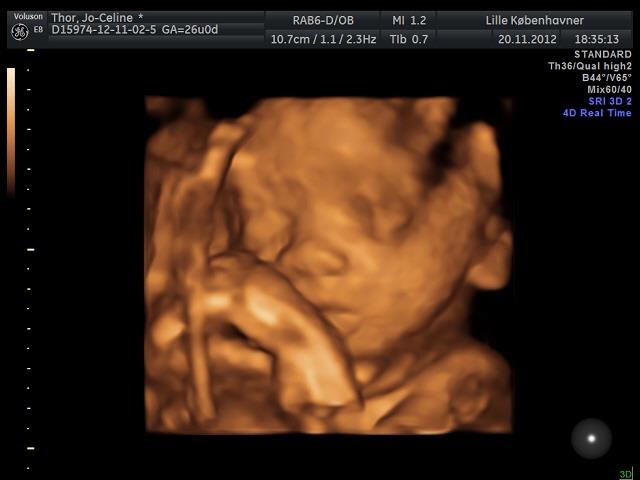

Synes også Lille Kbh'er var dårlige (var afsted før uge 12 i en graviditet sidste år som endte i en MA), og der var kvaliteten rigtig ringe men de har fået uddannede JM ind og fået nyt udstyr så gav dem en chance og kan kun give

for deres service og kvalitet nu. Ihvertfald deres 3D HD.

Du kan lige se et billede af vores pige i 3D 26+0

Vedhæftede fotos (klik for at se i fuld størrelse)